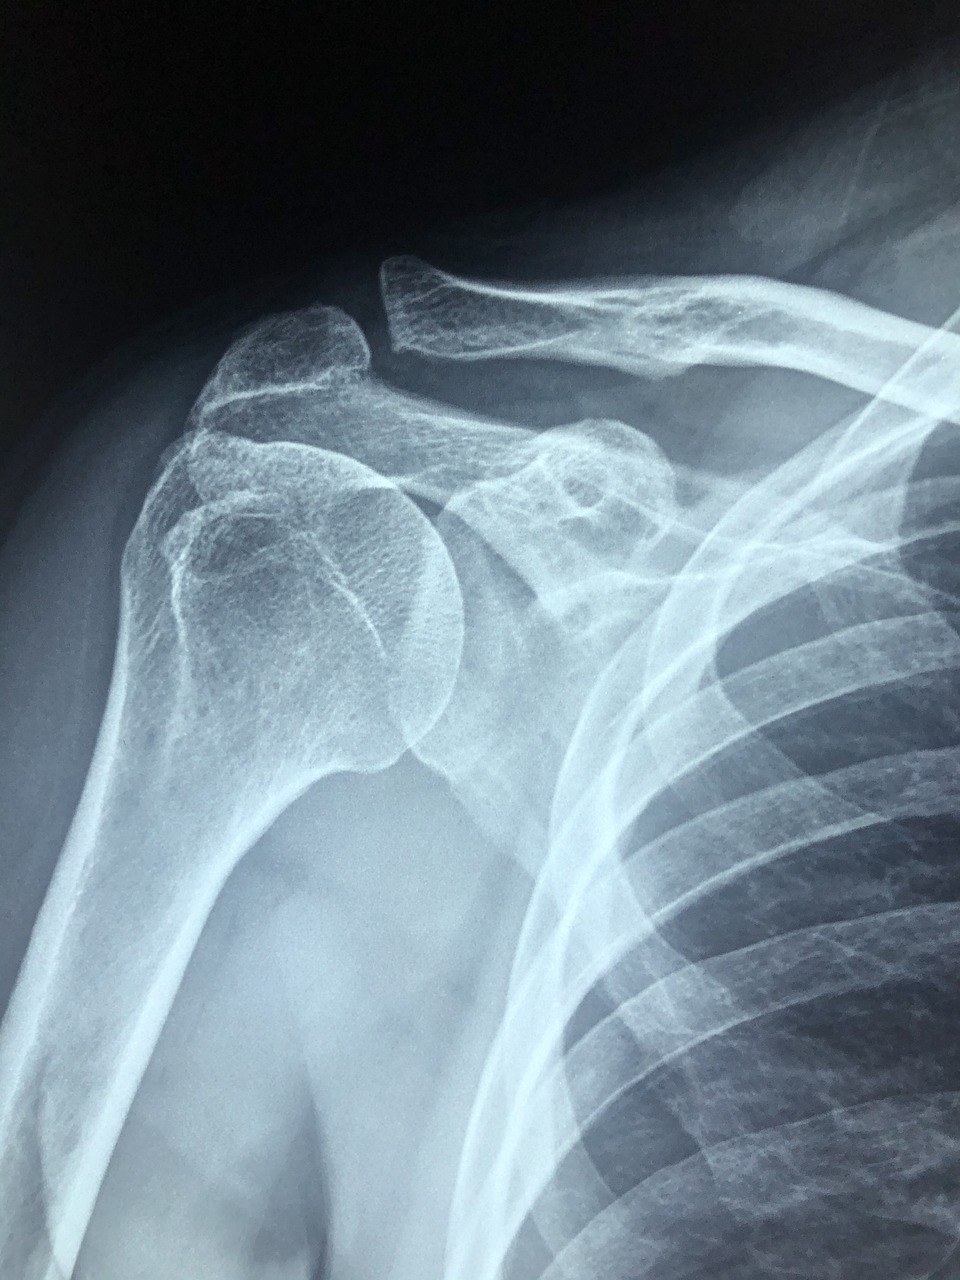

● 석회성건염

✅ 석회성건염, 테니스엘보

석회성건염은 어깨 회전근개에 석회 물질이 쌓여 극심한 통증을 유발하는 질환입니다. 체외충격파는 석회를 분해하고 흡수되는 과정을 촉진시켜 증상을 완화합니다. 이 경우 치료 기간은 비교적 길 수 있으며, 5~7회까지도 필요할 수 있습니다.